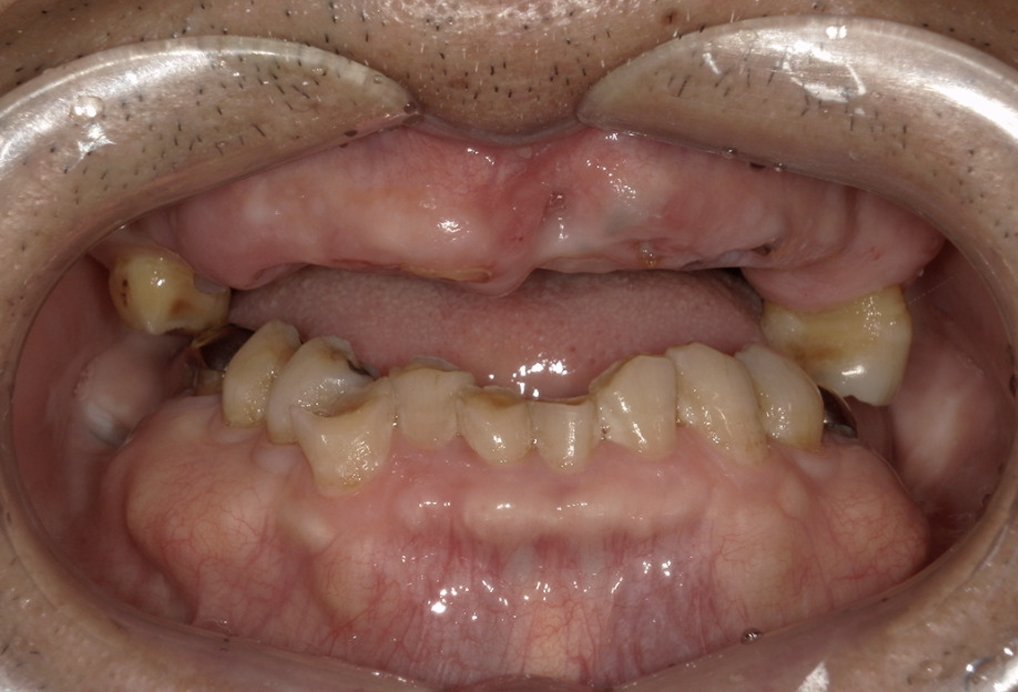

| 主訴 | 上の歯がぐらぐらする |

|---|---|

| 治療内容 | 上顎の歯が重度の歯周病のため全て抜歯し、

上顎に対するインプラント治療を行った。 午前中にインプラントの土台を入れ、夕方に上部構造(歯)を装着。 1日で噛めるようになる治療法。 |

| 治療期間 | 1日 |

| 治療費 | 250万円 |

| 治療 リスク | インプラント治療後2、3日はやや痛みを伴うことがあります。 |